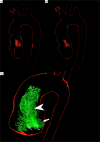

4D flow MRI enables quantitative assessment of helical flow. Current methods are susceptible to noise. To evaluate helical flow patterns in healthy volunteers and patients with bicuspid aortic valves (BAV) at 1.5 T and 3 T using pressure-based helix-extraction in 4D flow MRI. Two intraindividual 4D flow MRI examinations were performed at 1.5 T and 3 T in ten healthy volunteers (5 females, 32 ± 3 years) and 2 patients with BAV using different acceleration techniques (kt-GRAPPA and centra). Several new quantitative parameters for the evaluation of volumes [ml], lengths [mm] as well as temporal parameters [ms] of helical flow were introduced and analyzed using the software tool Bloodline. We found good correlations between measurements in volunteers at 1.5 T and 3 T regarding helical flow volumes (R = 0.98) and temporal existence (R = 0.99) of helices in the ascending aorta. Furthermore, we found significantly larger (11.7 vs. 77.6 ml) and longer lasting (317 vs. 769 ms) helices in patients with BAV than in volunteers. The assessed parameters do not depend on the magnetic field strength used for the acquisition. The technique of pressure-based extraction of 4D flow MRI pattern is suitable for differentiation of normal and pathological flow.